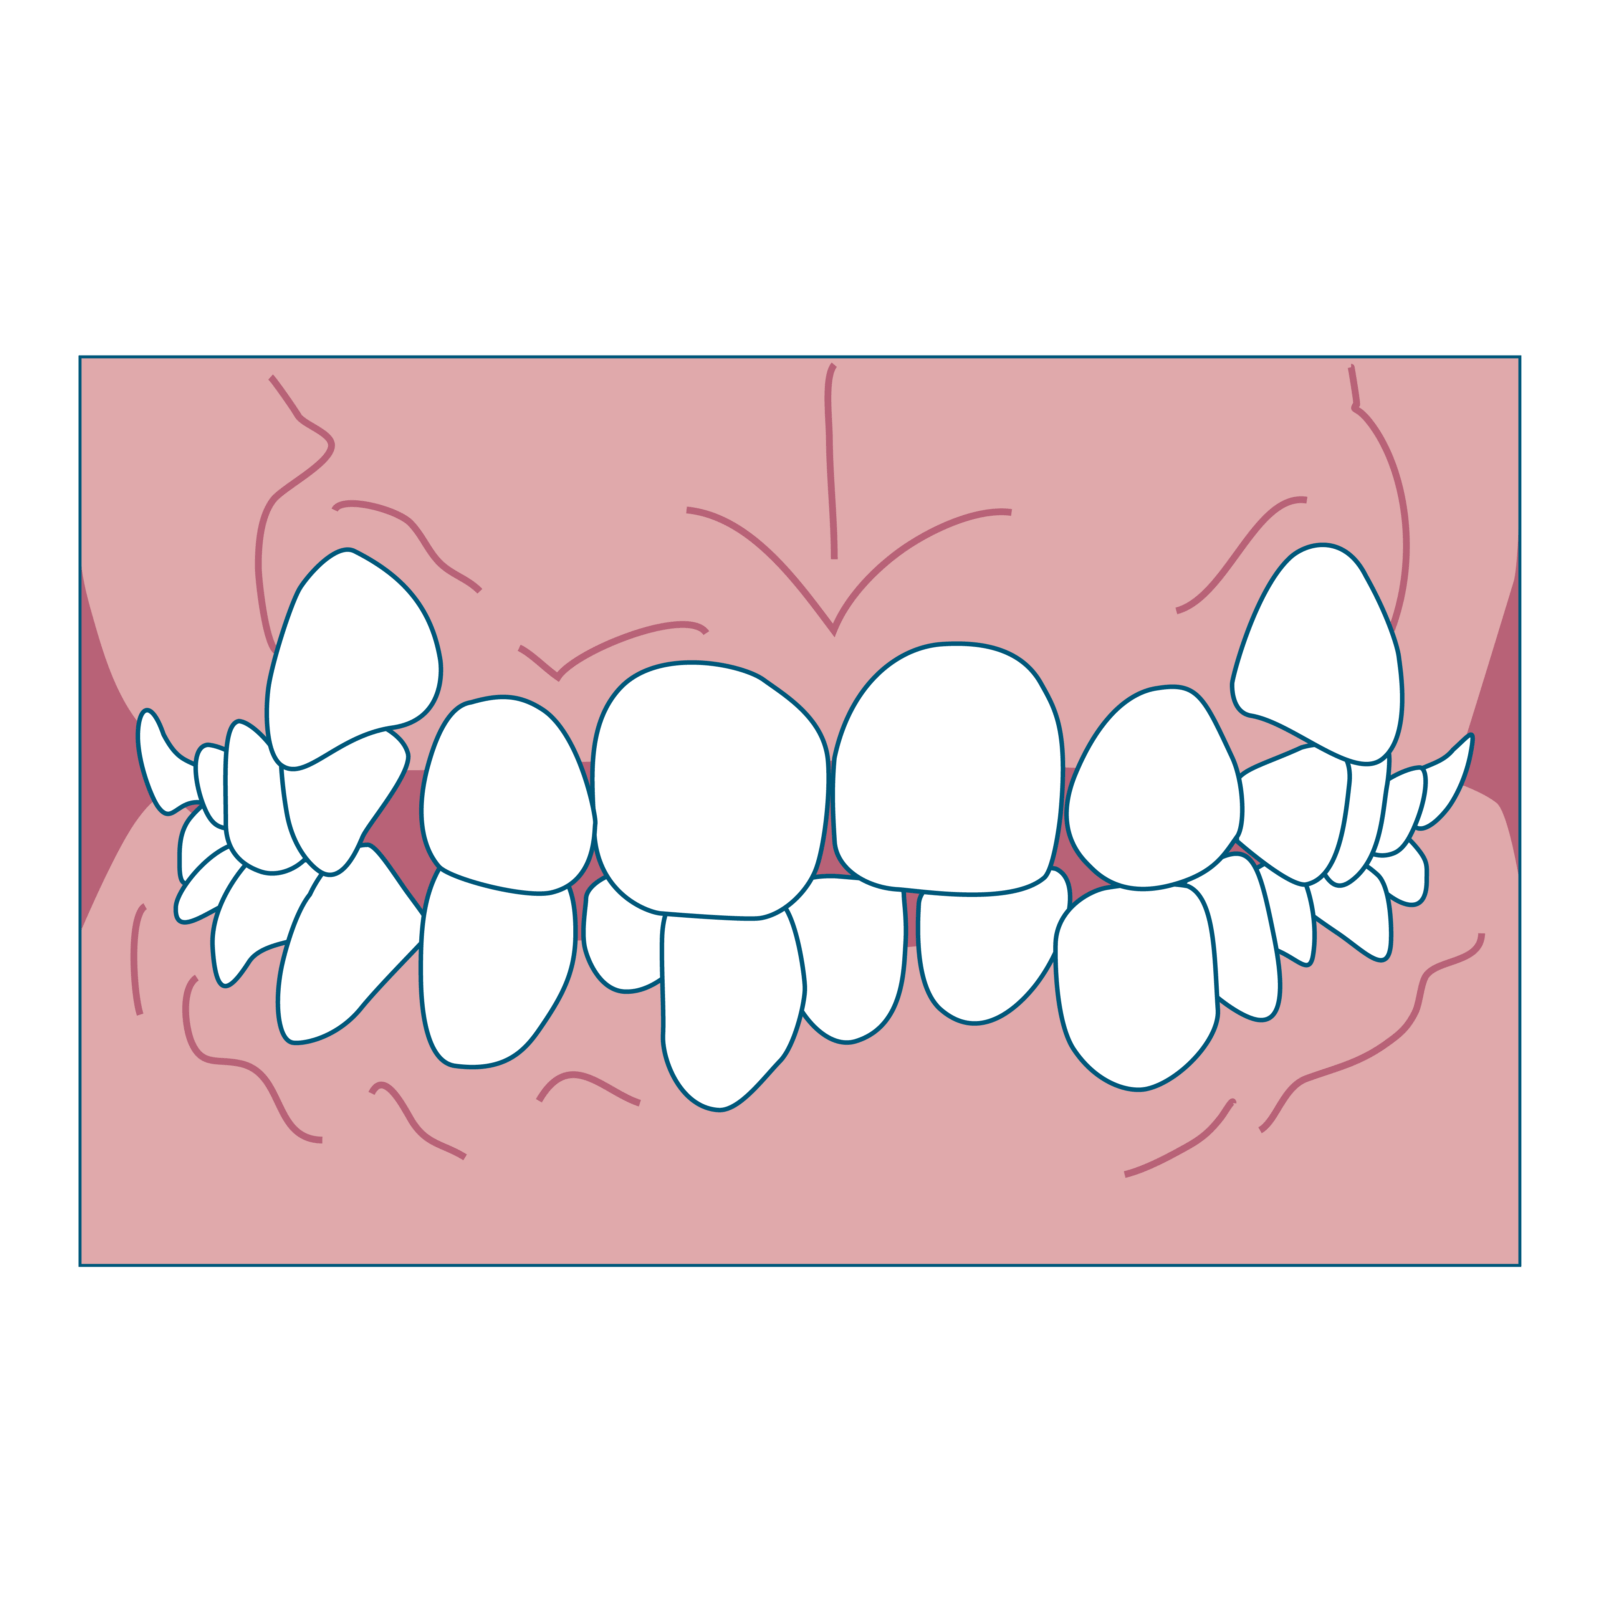

③ デコボコ(叢生/歯が重なっている)

特徴

- 永久歯が生えるスペースが足りず、歯が重なって生えてくる

- 歯磨きがしづらく虫歯や歯肉炎になりやすい

始め時

治療開始時期の目安は、 上下の前歯4本ずつ(すべて永久歯)と6歳臼歯が生えてきたタイミングです。年齢でいうと6~8歳頃となります。デコボコになる原因は、上下の顎(歯列弓・しれつきゅう)の大きさに対して、生えてきた永久歯が大きいと並ぶスペースが足りなくなることです。上あご下あごの前後的位置に問題がなく、上記の歯が生えていればいつでも開始することができます。

ワンポイント

乳歯の早期脱落やむし歯による抜歯は、スペース不足を悪化させる原因になるので注意が必要です。